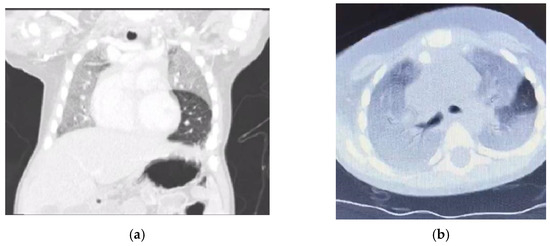

Six months ago, he presented with cough, dyspnoea, and desaturation, requiring admission to the pediatric intensive care unit (PICU) and ventilation for 2 days. Computerized tomography (CT) of the chest (Figure 1) showed diffuse homogenous ground glass opacity with interstitial septal thickening, which was interpreted by the primary physician as a picture of childhood interstitial lung disease (ChILD) and there was a subsequent prescription of steroids and hydroxychloroquine. He partially responded to treatment and was later discharged home on oxygen by nasal cannula.

Figure 1.

(a) CT chest, coronal cut, and lung window with homogenous opacity sparing of lingula but no feature of air trapping or attenuated blood vessels. (b) Computed tomography scan chest axial view; lung window ground glass opacity and septal thickening could suggest crazy paving.

Niemann–Pick disease type C2 is predominantly respiratory, in contrast to NPC1 [7,8]. There are three types of pulmonary alveolar proteinosis (PAP): autoimmune (the most common), hereditary, and secondary PAP, and coexistence between NPD and PAP is well established in the literature [9,10]. The coexistence of NPD and PAP is the main presentation of NPC2, leading to respiratory failure [11,12]. Similarly, our patient presented with progressive respiratory insufficiency. Furthermore, the instillation of olive oil in his nostrils with possible lipoid pneumonia possibly worsened the respiratory status of our patient [13]. Moreover, the chest X-ray showed homogenous opacity involving the entire right lung and the upper and middle zones of the left lung with an air bronchogram, and the chest CT showed a ground glass appearance together with intrapulmonary fat infiltrate with a Hounsfield unit score of −40 HFU (−40 to −130) PAP [14,15]. Our case showed ground glass opacities, mild smooth interlobular septal thickening, and intralobular lines as a crazy-paving pattern that could suggest a diagnosis of NPD with no evidence of emphysematous lobe, which has been reported as a sign of NPC2 [16,17].